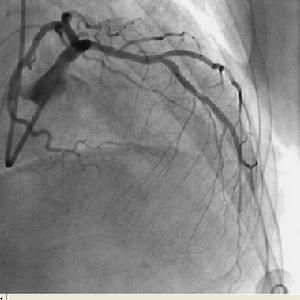

本病是由於後內乳頭肌靠近室間隔,只接受後降支和左迴旋支供血,距離左右冠狀動脈開口都較遠,所以血運比前外乳頭肌差,加之瓣膜退變或心肌梗死,因此出現乳頭肌功能不全和斷裂。